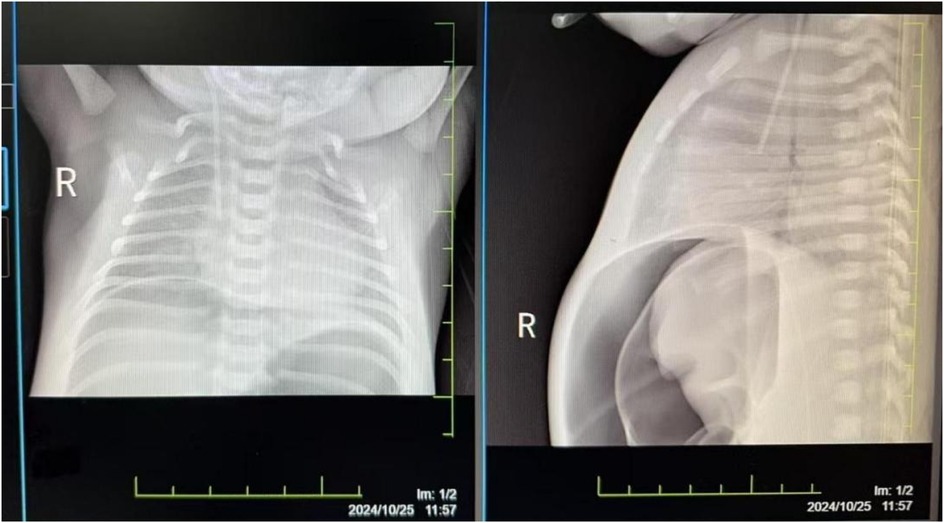

Umbilical cord blood gas analysis revealed severe acidosis (pH 6.68, BE −26.6 mmol/L) with hypercapnia (PCO2 105.7 mmHg) and hyperlactatemia (13.26 mmol/L); admission blood gas analysis showed acidosis (pH 6.89, BE −26.7 mmol/L, lactate 14.71 mmol/L). Hematologic testing indicated anemia (Hb 110 g/L), with marked coagulopathy (PT 106.7 s, APTT 126.8 s, FIB 0.19 g/L, D-dimer 111.6 µg/ml). Cardiac enzymes were elevated (TnI 0.191 ng/ml, CK 629 U/L, CK-MB 200 U/L), while liver function tests showed hypoproteinemia (TP 18.9 g/L) and elevated AST (269 U/L); renal function was normal (Crea 63 µmol/L). Echocardiography identified a patent ductus arteriosus (PDA) with right-to-left shunting, mild pulmonary hypertension (pulmonary artery systolic pressure, PASP 36 mmHg). Cranial ultrasound suggested subependymal hemorrhage (increased echogenicity), and lung ultrasound revealed dense B-lines bilaterally. Abdominal imaging showed renal pelvis separation and enhanced parenchymal echogenicity, while chest x-ray demonstrated coarse lung markings. Amplitude-integrated EEG (aEEG) showed discontinuous normal voltage with an immature sleep-wake cycle. Hemodynamic monitoring (ICON device) revealed elevated intrathoracic fluid (66 ohms1) and myocardial contractility (192.9), with a cardiac index of 4.6 L/min/m2². Cranial MRI at 2 weeks confirmed cerebellar hemorrhagic foci, and ophthalmic screening at 4 weeks detected stage 1 retinopathy in zone III bilaterally. Blood and sputum cultures were negative, and the neonatal behavioral neurological assessment (NBNA) score at discharge was 37.